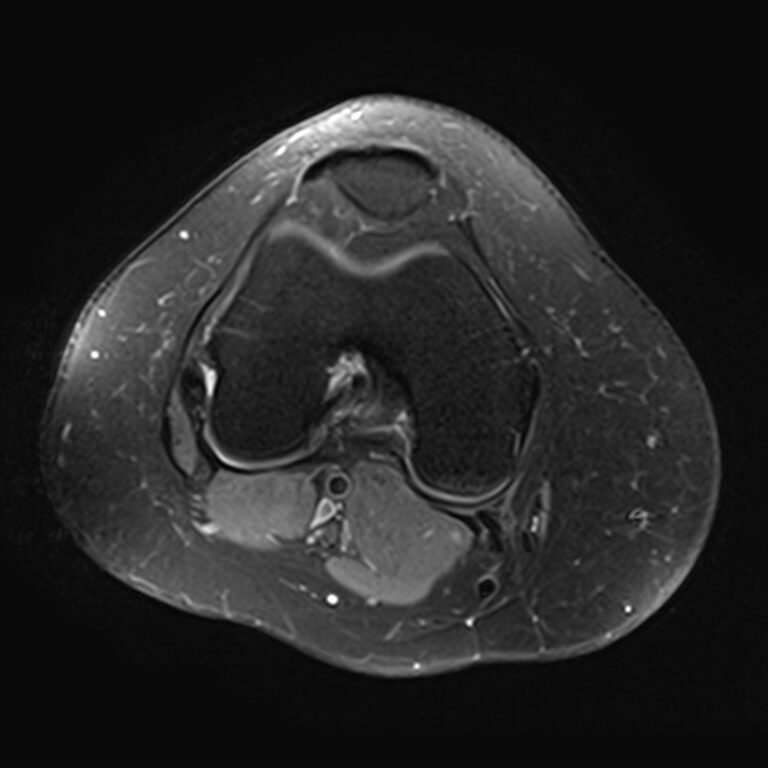

Магнитно-резонансная томография является высокоинформативным методом выявления причин возникновения заболеваний коленного сустава. В клинике «Доступная медицина» диагностика осуществляется на новейшем высокопольном томографе закрытого типа TOSHIBA VANTAGE TITAN 1,5 Тесла, обеспечивающем высочайшее качество изображений исследуемой зоны.

Томограф позволяет детально визуализировать как костные структуры колена, так и окружающие мягкие ткани данной анатомической области, включая мышцы, связки, нервные сплетение, сосуды.